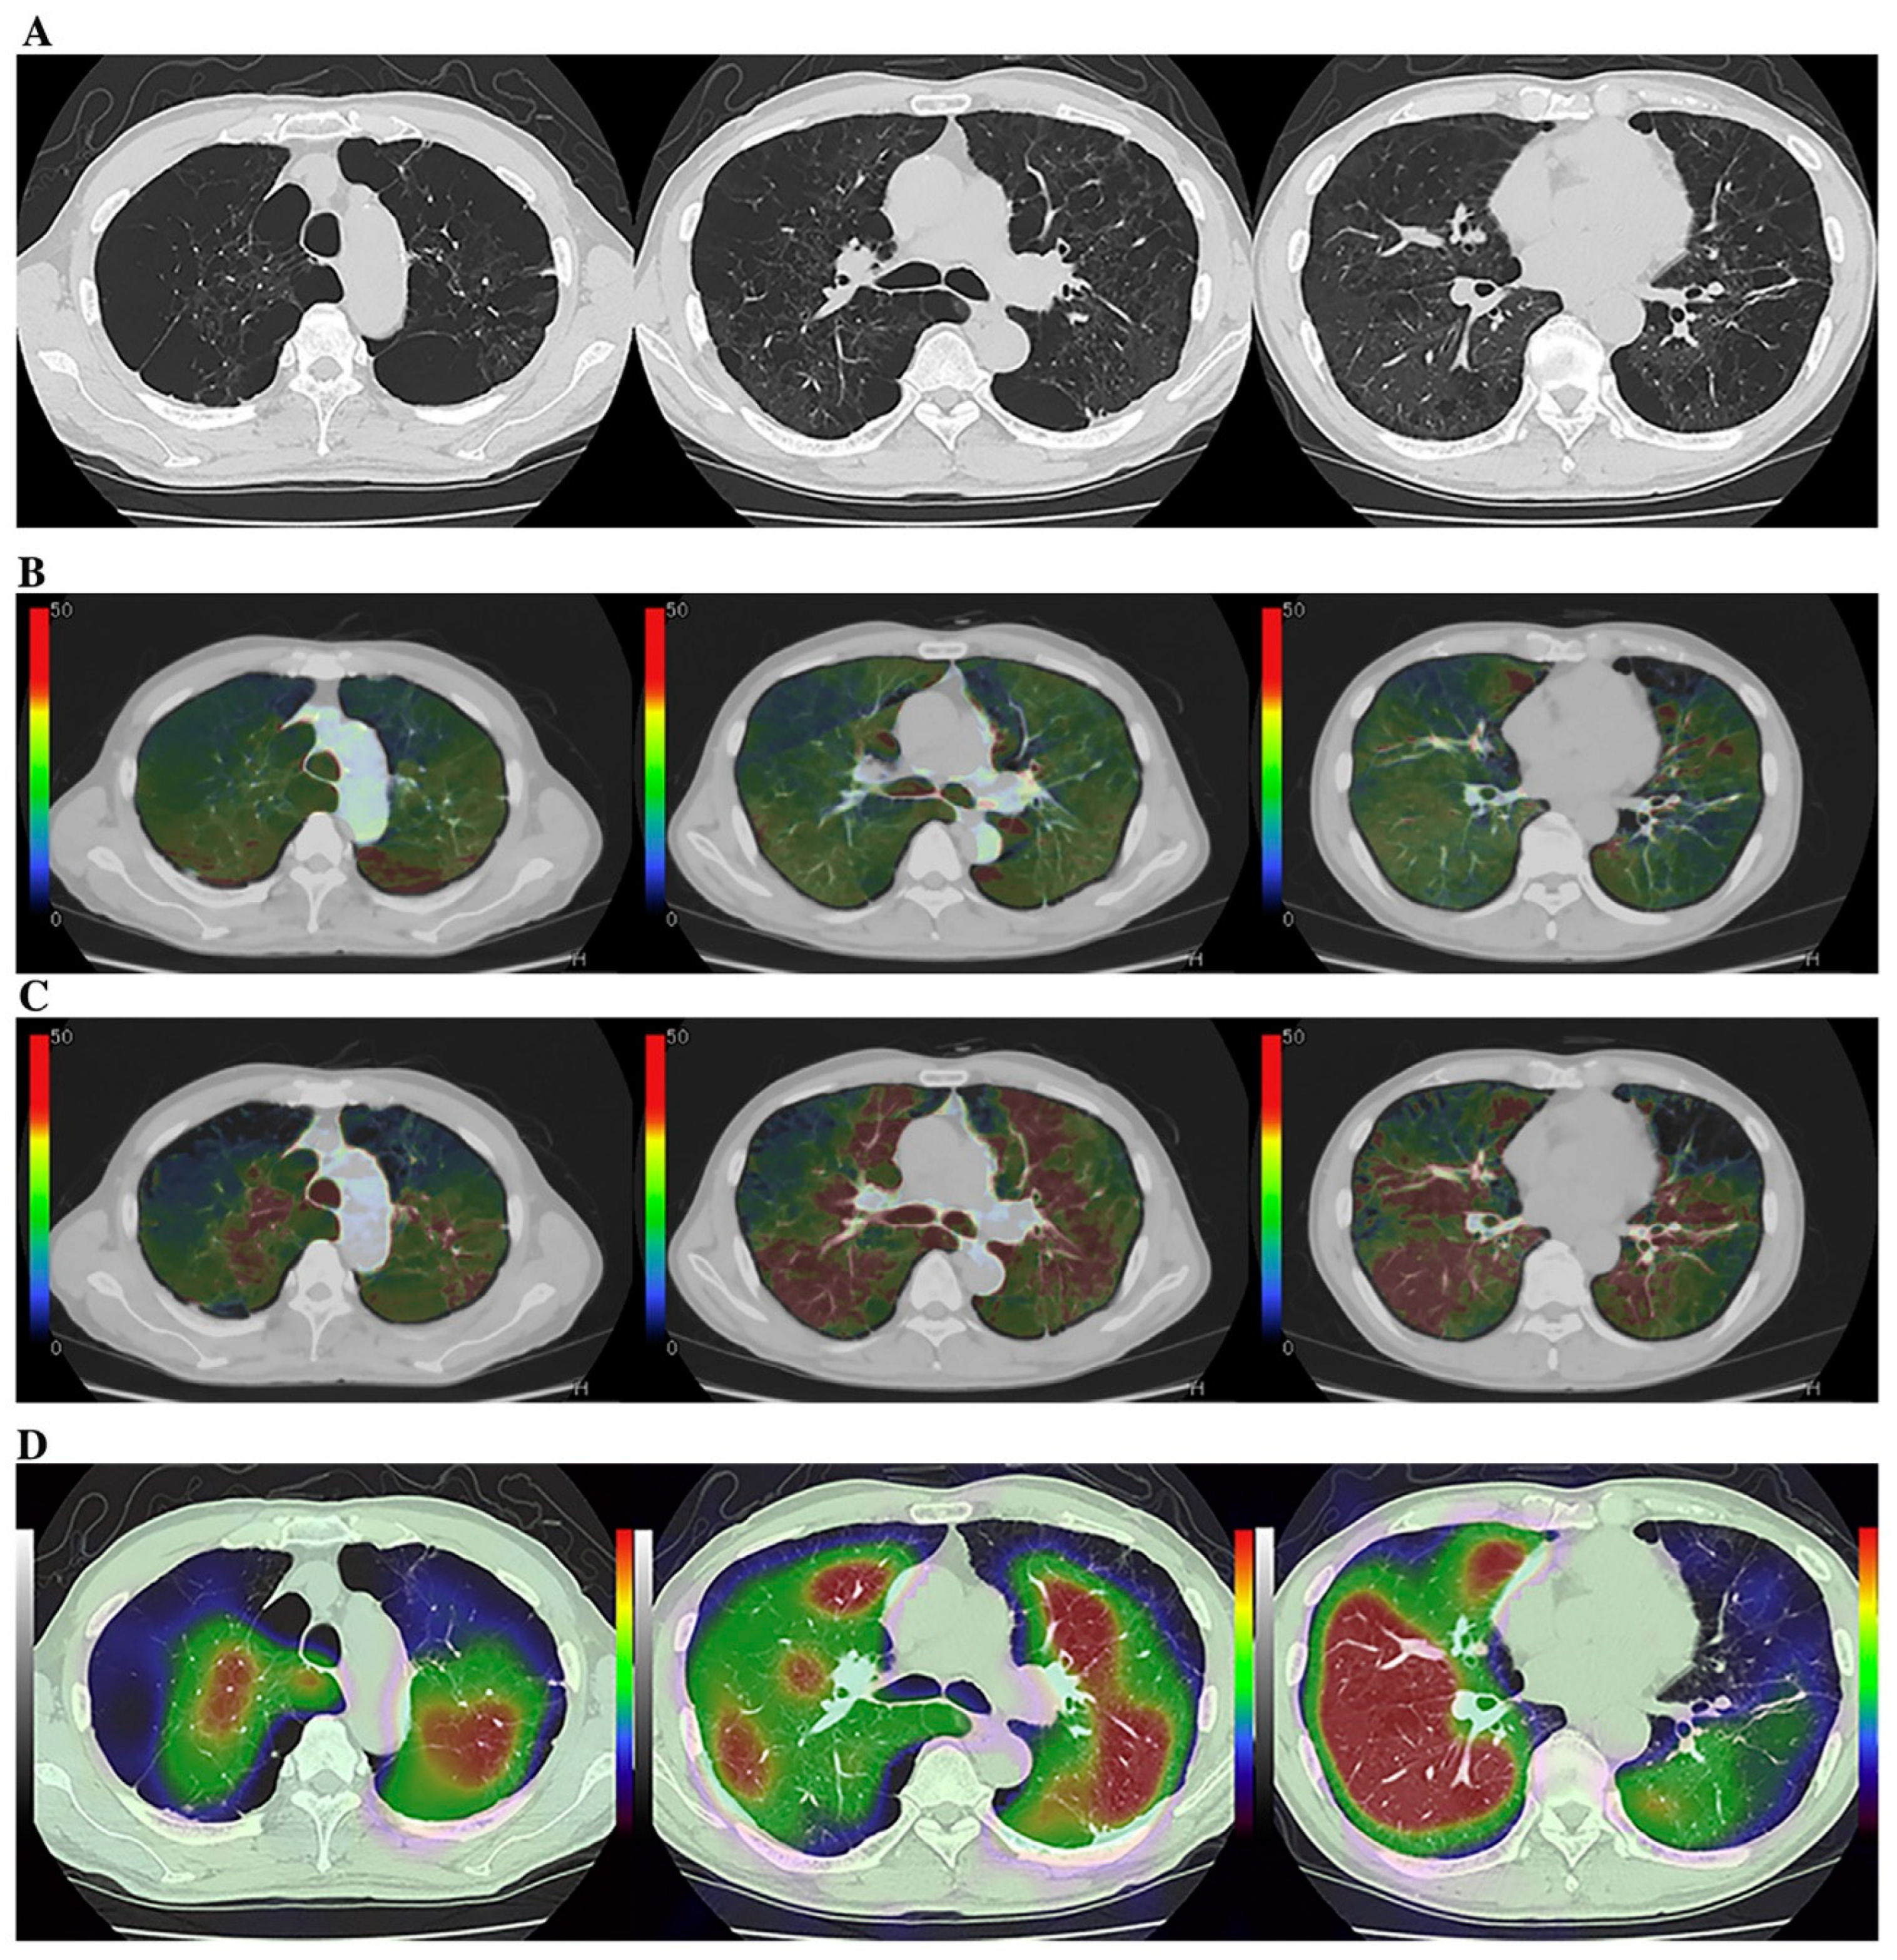

Few studies have been published on radiation dose reduction for the use of ADCT for the quantitative assessment of morphological evaluation of ILD. However, the utility of commercial or proprietary artificial intelligences (AIs) using machine-learning methods by Canon Medical Systems has been evaluated for the management of various lung diseases, such as ILD, or the evaluation of therapeutic treatments for coronavirus disease 2019 (COVID-19) pneumonia, which is caused by severe acute respiratory syndrome coronavirus 2 (SARS-CoV-2) [61,62,63] (Figure 2).

Figure 2.

A 65-year-old female patient with progressive scleroderma (top row, L to R: thin-section CT scans at baseline, acute exacerbation phase, and after-treatment phase; bottom row, L to R: CT texture analysis by means of machine-learning-based software at baseline and the same two phases as for the top row) (permission from reference [63]). On machine-learning software, normal lung, consolidation, emphysema, GGO, honeycombing and reticulation are expressed as blue, beige, purple, green, red and green. A comparison of CT scans obtained at baseline (i.e., “Stable” group) and at the acute exacerbation phase (i.e., “Worse” group) shows an increase in the GGO and the consolidation area and a decrease in the normal lung area. Δ% normal lung, Δ% GGO, and Δ% consolidation were −16.9%, 13.2%, and 2.5%, respectively, while Δ disease severity score was 6. A comparison of CT scans obtained at the acute exacerbation phase (i.e., “Worse” group) and the after-treatment phase (i.e., “Worse” group) shows an increase in the GGO, reticulation, and honeycomb area and a decrease in the normal lung area. Δ% normal lung, Δ% GGO, Δ% reticulation, and Δ% honeycomb were −19.5%, 14.9%, 4.2%, and 0.2%, while Δ disease severity score was 15. CT, computed tomography; GGO, ground-glass opacity.

These studies were the first to demonstrate the potential of AI in the evaluation of disease severity and therapeutic effect or of functional changes due to treatment with an accuracy similar to that attained by board-certified radiologists [61,62,63]. Although further investigations are warranted, the evaluation of ADCT by AI has opened new areas for the application of pulmonary functional ADCT in not only ILD but also other diseases.